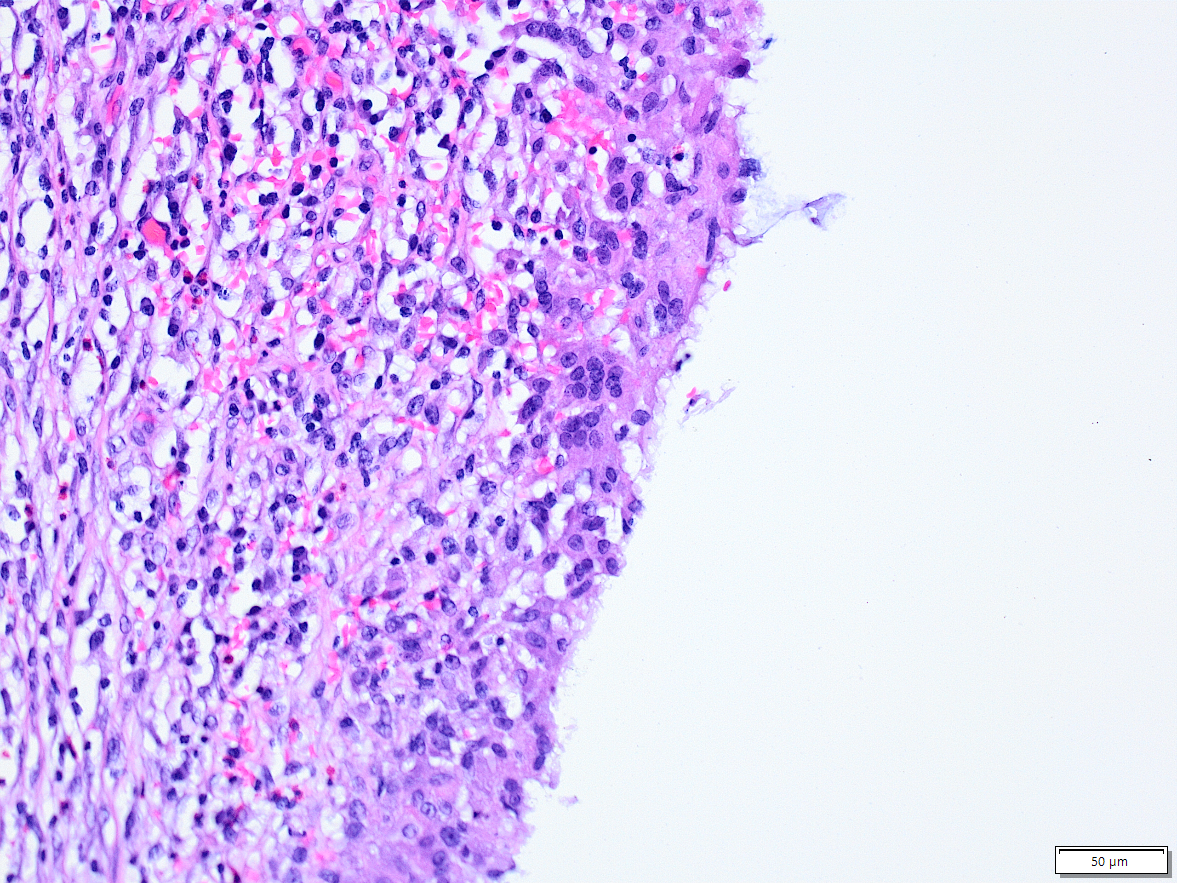

4. Stellenweise ist das Epithel ganz weg. Hier haben zu Riesenzellen fusionierte Makrophagen (also Zellen des Immunsystems) eine Barriere gebildet. Das finde ich Spannend.

Nota bene: An keiner Stelle zeigt sich ein eindringen der Pilze in den Körper!

5. Es kommt aber was aus dem Körper in den Pilz: Neutrophile Granulozyten (also Träger der akuten Entzündung), kommen und "kämpfen" gegen den Pilz.